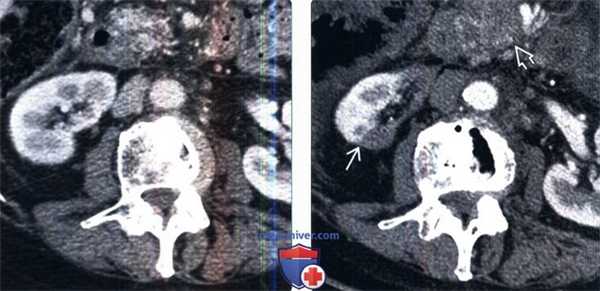

(Слева) Женщина 72 лет с анамнезом неоперабельной аденокарциномы поджелудочной железы подверглась внешнему лучевому воздействию. На КТ почек с контрастированием, в аксиальной срезе, спустя пять месяцев после облучения не обнаружено никаких существенных изменений.

(Справа) При повторном исследовании, выполненном спустя пятнадцать месяцев после внешнего лучевого воздействия определяется атрофия и заметное снижение перфузии медиальной поверхности правой почки вдоль места облучения. Обратите внимание на четкую границу между нормальной и пораженными частями почки. Также следует обратить внимание на образование поджелудочной железы.